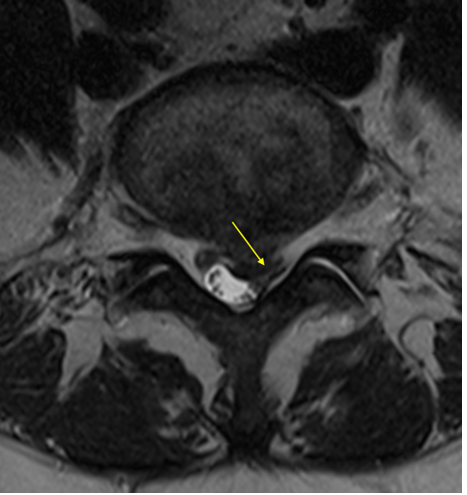

An MRI of the lumbar spine revealed a large L5/S1 disc extrusion in the sub-articular zone that deformed the thecal sac with posterior displacement of the left S1 nerve root (Image 1). An L4/5 central disc protrusion and annular fissure were visualized (Image 2).

Axial T2WI

(Image 1) Axial T2WI